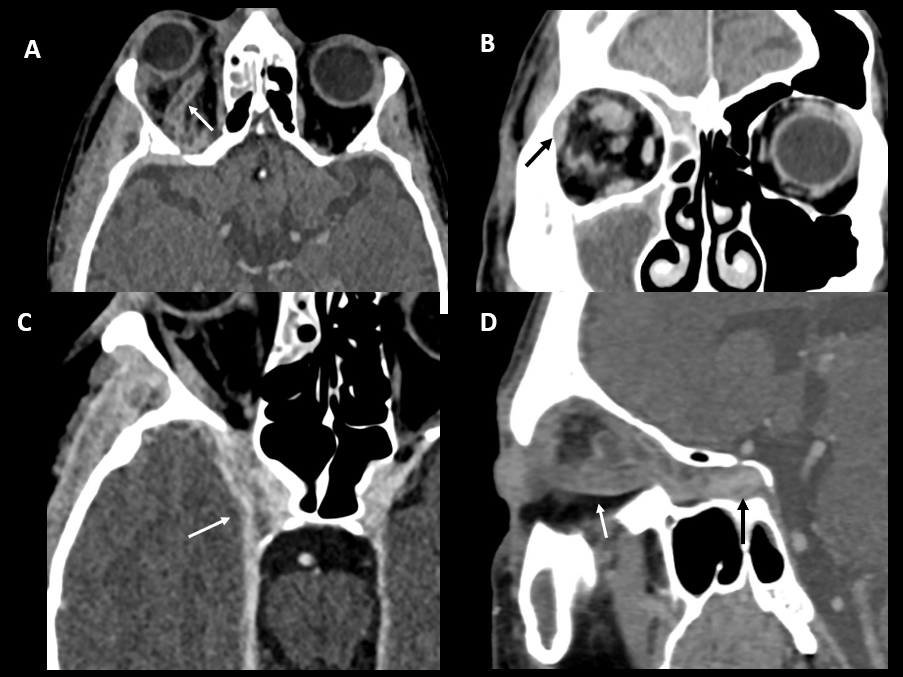

Imagen A: TC con contraste, plano axial. Exoftalmos y defecto de repleción con ingurgitación de una vena oftálmica (flecha).

Imagen B: TC con contraste, plano coronal. Aumento de densidad a nivel intraorbitario extraconal (flecha), con amplio contacto con la pared lateral de la órbita.Trabeculación de la grasa intraconal.

Imagen C: TC con contraste, plano axial. Asimetría del seno cavernoso derecho, expandido (flecha), con hipodensidad de morfología lineal en su interior.

Imagen D: TC con contraste, plano sagital oblicuo. Defecto de repleción con ingurgitación de la vena oftálmica (flecha blanca) y del seno cavernoso (flecha negra).

Dg: Celulitis postseptal complicada con trombosis de vena oftálmica y del seno cavernoso, y absceso intraorbitario extraconal.